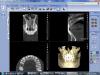

Hercule Опубликовано 25 ноября, 2012 Поделиться Опубликовано 25 ноября, 2012 (изменено) Здравствуйте!Год назад сломался передний зуб и на снимке обнаружили кисту.26 Апреля 2012 года была проведена резекция корня.3 Июля сделана 3Д томограмма Planmeca_Romexis_Viewerвот тут её можно скачать.http://files.mail.ru/697LNM Подскажите, пожалуйста, всё ли там хорошо в районе 1-го справа.Ничего не болит, только едва заметно периодически отекает И что можно сказать по поводу правой гайморовой пазухи. Вопросы всвязи с тем, что не могут ли эти места быть источником хронической инфекции.У меня хронический гастрит, хронический панкреатит и подозрение на хронический миокардит. Спасибо! Изменено 25 ноября, 2012 пользователем Hercule Ссылка на комментарий

Hercule Опубликовано 25 ноября, 2012 Автор Поделиться Опубликовано 25 ноября, 2012 28 ноября :Апрель перед резекцией:Май после резекции:Июль после резекции: Скриншоты от 3Д Ссылка на комментарий